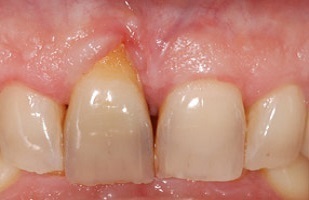

- Cas 1:

Dans une volonté de discrétion et de naturel, le patient a demandé que la couronne sur implant soit aussi jaune que la dent naturelle remplacée